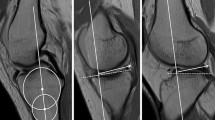

To plan the number of cases, we performed a power analysis with a 95% confidence interval and a width of 0.4. A collective size of 116 cases per group was determined. All knee joint MRIs performed at our center from 2018 to 2019 were examined until each of the groups was filled with 116 patients according to the inclusion criteria. In the group without ACL rupture, all MRIs were included that had no ligamentous injury and were older than 18 years. In the second group, all MRIs of the knee joint from patients over 18 years old with a confirmed ACL rupture were included. The examination was performed in the supine position in a 3 Tesla MRI (Ingenia 3 T Phillips). The sagittal MRI slices were set as true sagittal sequences. The cases were included only if there were no more than 3 days between the accident and the MRI. Retrospectively the tibial slope was measured by two independent orthopedic surgeons, a fellowship trained knee attending surgeon and a senior orthopedic resident in 116 MRI´s of patients with and in the same number of patients without an ACL rupture. The reviewers were blinded to the pathology and to each other´s results. The osseous as well as the cartilaginous slope was defined in the postero-latero-lateral (PLL) and postero-latero-central (PLC) segments of the tibial plateau using the 10-segment classification (Fig. 1). The PLL and PCL were determined by simultaneously checking the position in the axial images. In both segments, the osseous as well as the cartilaginous slope was measured. Intra- and inter-observer reliabilities were assessed. The measurements were repeated at an interval of 3 months with a random order of the studied knees.

MRI of a 31 healthy woman. I axial slice of the MRI with applied 10 segment classification. The red dash line with the II shows the sagittal slice through the PLC segment, III shows the sagittal slice through the PLL segment. ALL antero latero-lateral, ALC antero-latero-central, AC antero-central, AMC antero-medio-central, AMM antero-medio-medial, PLL postero-latero-lateral, PLC postero-latero-central, PC postero-central, PMC postero-medio-central, PMM postero-medio medial; II sagittal section of the MRI's from I in the position of the red dash line marked II; III sagittal section of the MRI from I in the position of the red dashed line marked III

Lateral tibial slope (LTS) were measured on sagittal MRI sequences according to the method described by Hudek et al. [22] (Fig. 2). This method has been reported to be the most repeatable method to measure sagittal tibial slopes on MRI and is independent of proximal tibial length [23]. First, the proximal anatomical axis of the tibia was defined on the central sagittal slice in which the attachment of the PCL and the intercondylar eminence were visualized, and both the anterior and posterior tibial cortices appeared in a concave shape. Within this slice, two circles were placed into the proximal tibia. The proximal circle was fit within the proximal, anterior, and posterior cortical borders. The distal circle was fit within the anterior and posterior cortices with the center of the circle positioned on the perimeter of the proximal circle. A line drawn through the centers of both circles defined the proximal anatomical axis of the tibia. Next, the sagittal slice showing the center of the PLL and PLC segment of the lateral plateau were identified. In the PLL as well as in the PLC a tangent to the uppermost even part between the superior anterior and posterior cortices was drawn. For the cartilaginous slope, the tangent was applied to the cartilage layer seen on MRI. The PLL slope, as also the PLC slope, was defined as the angle between the orthogonal to the proximal anatomic axis of the tibia and the tangent. All measurements were made in digital at our PACS system.

Measurement of tibial slope in the PLC and PLL segment according to Hudek et al. in a 31-year-old healthy woman. It shows the determination of the tibial shaft axis. The white line represents the tibial shaft axis and is defined by the centers of the two red circles. The proximal red circle is bounded by the anterior and posterior corticalis and the tibial plateau. The distal red circle is bounded by the anterior and posterior corticalis and the center of the circle lies on the circumference of the proximal circle; II sagittal MRI in the center of the PLC segment, the yellow line is the tangent representing the cartilaginous slope and the blue tangent represents the bony slope; III sagittal MRI in the center of the PLL, again the yellow line represents the tangent presenting the cartilaginous slope and the blue one the bony slope